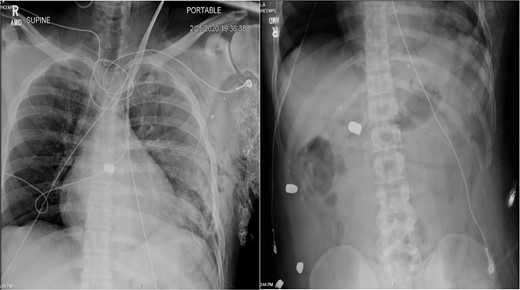

On hospital Day 7, the patient had acute hypoxic respiratory failure. CT chest found a right segmental pulmonary embolism and a retained bullet near the aortic root. A TEE was repeated, this time demonstrating severe aortic insufficiency (Fig. 4), and a bullet in the left coronary cusp. Cardiothoracic surgery was consulted for evaluation and management. The next day, the patient went to the OR for median sternotomy, cardiopulmonary bypass, aortic root repair with patch, re-attachment of the left coronary cusp, and removal of the bullet from the aortic root.

TEE with intracardiac bullet, severe aortic insufficiency. The bullet is labeled by an asterisk, with shadow artifact posterior to the bullet.

Case 2 involved a hemodynamically unstable patient with multiple thoracoabdominal GSWs. The surgical team identified six GSWs and five retained bullets. The patient’s instability precluded CT imaging. A cardiac injury was suspected due to a bullet overlying the cardiac silhouette and significant chest tube output. Thoracotomy confirmed a cardiac injury with tamponade, necessitating immediate repair. The bullet trajectory suggested it passed through the heart and diaphragm into the abdomen. TEE revealed no intracardiac shunting, valve insufficiency, or bullet. The bullet injured the left ventricle and embolized to the aortic root, becoming symptomatic on hospital Day 7. A CT scan suggested an intravascular bullet near the aortic valve, confirmed by TEE showing severe aortic insufficiency. The patient required four operations for definitive management. This case underscores the risks of conservative management and the need for thorough evaluation in unstable patients.